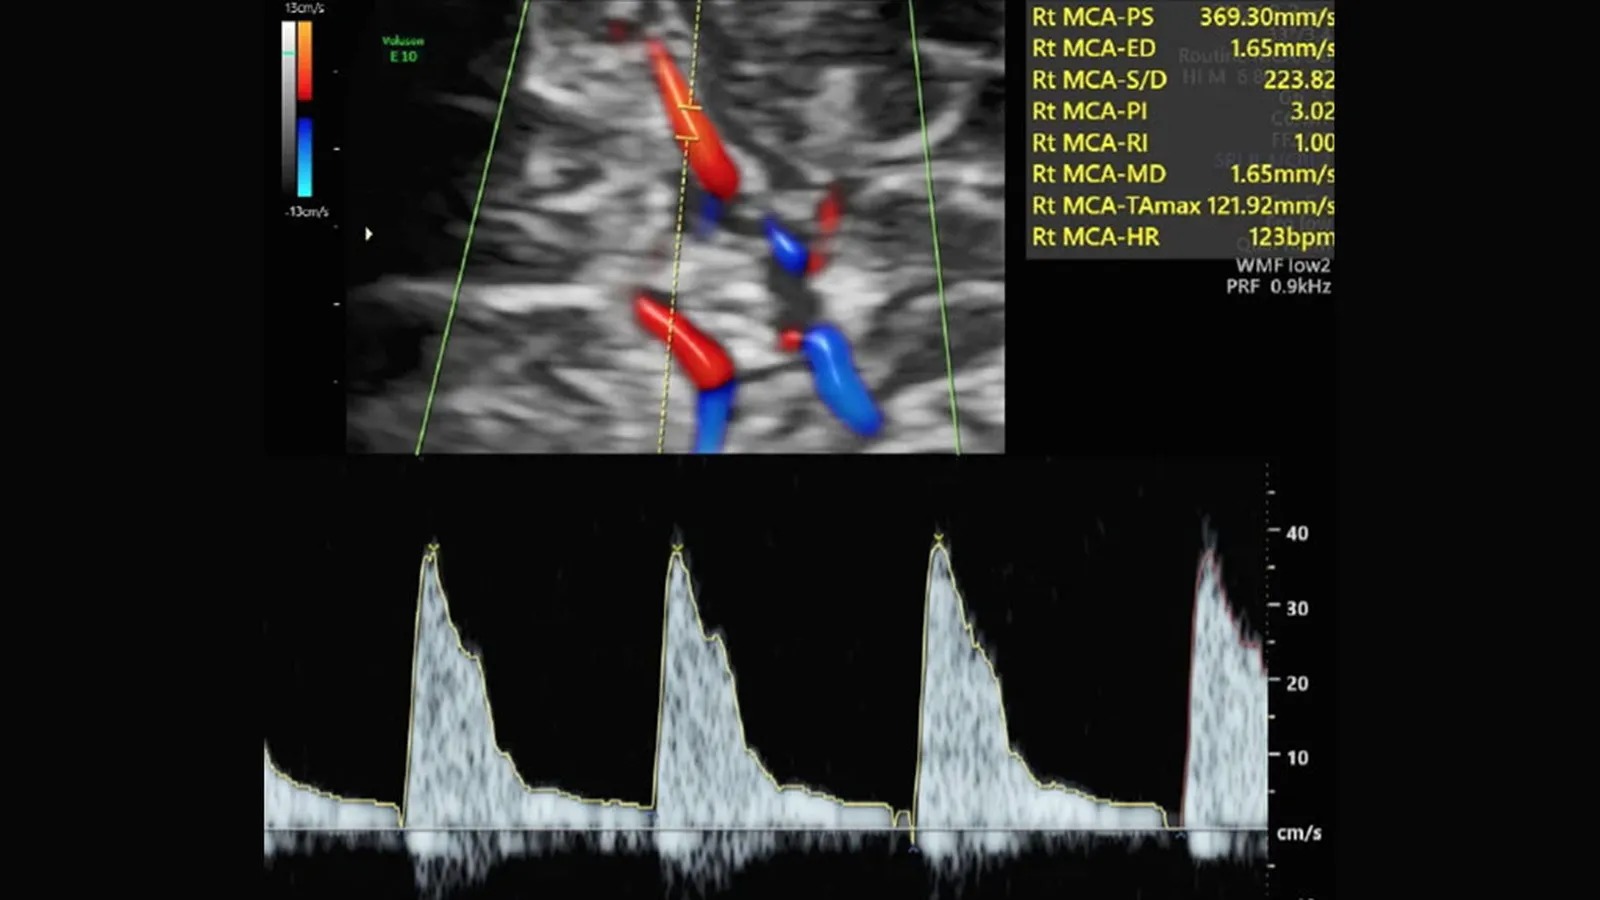

(Fundación ˝la Caixa˝).- Determinar el flujo de los vasos del cerebro del feto y de la placenta mediante Doppler en la ecografía de rutina del tercer trimestre permite detectar a bebés en riesgo de presentar complicaciones posparto que requieran ingreso en la UCI. Inducir el parto al término de la gestación en esos casos de riesgo podría reducir a la mitad la tasa de ingreso en la UCI neonatal. Así lo demuestra un estudio internacional multicéntrico denominado RATIO37 y publicado en la revista The Lancet.

Una prueba con ecografía Doppler que mide la circulación de la sangre por el cordón umbilical y el cerebro, denominada ratio cerebro-placentario (o RCP), puede detectar la insuficiencia placentaria. Hasta ahora, esta prueba solo se realizaba en embarazos con problemas, en casos muy indicados. Desde hace más de 10 años ha existido un debate en el mundo científico sobre si había que medir el RCP en todas las embarazadas o era un gasto de recursos innecesario. Si la prueba Doppler se llevara a cabo en todos los embarazos, tal vez serviría para mejorar la detección de bebés con riesgo de complicaciones por insuficiencia placentaria. Pero también existiría el riesgo de que la prueba no mejorase nada y, en cambio, solo generase más gasto y angustia en las madres.

En el estudio RATIO37 han participado durante 6 años más de 11.500 mujeres con embarazos de bajo riesgo. En la ecografía de las 36 semanas se midió el RCP en todas las mujeres, pero las participantes fueron divididas al azar en dos grupos. En unas, la prueba se utilizaba para cambiar el manejo de la gestación y, en caso de salir alterada, se proponía a la mujer una inducción precoz del parto al llegar al término. En las otras, el resultado de la prueba no se comunicaba y se manejaba el embarazo según los protocolos vigentes. El estudio comparó los números de casos de muerte del bebé y de complicaciones neonatales graves (que incluían, entre otros, problemas neurológicos, intestinales, cardíacos, renales o respiratorios, con una estancia en la UCI de 10 días o más) que se producían en cada grupo.